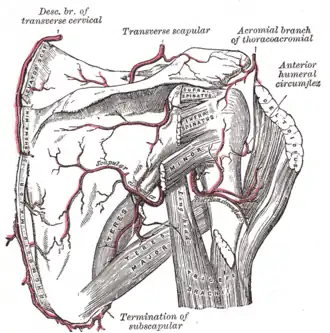

There is a ridge on the outer part of the back of the scapula. This runs from the lower part of the glenoid cavity, downward and backward to the vertebral border, about 2.5 cm above the inferior angle. Attached to the ridge is a fibrous septum, which separates the infraspinatus muscle from the Teres major and Teres minor muscles. The upper two-thirds of the surface between the ridge and the axillary border is narrow, and is crossed near its center by a groove for the scapular circumflex vessels; the Teres minor attaches here.

The scapular and circumflex arteries.

The scapular and circumflex arteries. -